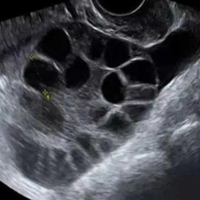

备孕是一件非常重要的事情,很多准备要孩子的夫妻都非常关心如何提高成功率。卵泡监测是备孕过程中非常常见的一种方法。但是,备孕有必要监测卵泡吗?下面我们来详细讨论一下。什么是卵泡监测卵泡监测是通过超声波或其他诊断手段,及时观察女性卵巢里的卵泡发育状况,判断卵泡大小、数量、位置、形态等指标,以便确定排卵期和最佳受孕时机。卵泡监测有哪些方法目前比较常用的卵泡监测方法有以下几种:经腹超声检查 、经阴道超声检

备孕是一件非常重要的事情,很多准备要孩子的夫妻都非常关心如何提高成功率。卵泡监测是备孕过程中非常常见的一种方法。但是,备孕有必要监测卵泡吗?下面我们来详细讨论一下。什么是卵泡监测卵泡监测是通过超声波或其他诊断手段,及时观察女性卵巢里的卵泡发育状况,判断卵泡大小、数量、位置、形态等指标,以便确定排卵期和最佳受孕时机。卵泡监测有哪些方法目前比较常用的卵泡监测方法有以下几种:经腹超声检查 、经阴道超声检

有女性在监测卵泡的时候千万不要做阴超这种说法的原因是B超探头会经由阴道进行检查,会产生一定的疼痛感,此外,在监测卵泡的时候做阴超稍有不慎就可能会对身体带来一定的损伤,阴道彩超检查需要将探头放入女性的阴道,如果在检查时没做好消毒工作,检查时容易引起感染,可能会导致阴道炎、宫颈炎等疾病发生,操作不当还会导致患者出现异常的阴道流血。实际上,在进行卵泡监测时,常常使用阴道超声来观察和测量卵泡的大小和发育情

大姨妈走后10天左右是b超查卵泡的最佳监测时间。一般情况下,女性月经周期是30天左右,通常在下次月经开始前的14天进行排卵。而查卵泡最好是在卵泡生长的早期阶段进行监测,这样可以帮助确定卵泡的数量、大小和生长情况,为后续的生育或者健康状况提供重要的信息。卵泡监测是女性生殖内分泌科常见的一种检查,可以通过B超进行监测,能够观察到卵泡的发育情况。而卵泡的发育是随着月经的周期而变化的,一般的在下次月经前1

女性在平时的生活中如果不注意保养身体就很容易出现卵巢异常的情况,这种情况就会影响到女性的受孕成功率。所以有些不孕的女性会进行卵泡监测,卵泡监测可以了解清楚卵泡的生长发育。那么卵泡监测从什么时候开始?卵泡监测从什么时候开始?查卵泡配塌的时间是从月经来潮的第1天开始一直到第11天的时候。目前监测卵泡的方法主要是通过阴道彩超进行,阴道彩超的优势在于无需喝水憋尿,如果监测时没有发现优势卵泡,可间隔1到2天

关于排卵监测,之前的文章也讲到过,有基础测体温法、排卵试纸监测法、看阴道分泌物、排卵痛疼痛法等。今天我们要说的是B超监测排卵法,这是观察卵泡发育、内膜厚度和确定排卵期最准确的方法。卵泡怎么检查卵泡对于女性的生育能力有特别大的影响,要是卵泡不良的话,就很容易使女性不孕。如果因为卵泡问题而影响到了生育的时候,就需要对卵泡进行检查、检测了,然后才能针对性的进行治疗。女性进行卵泡检查时,最常采用的就是通过

卵泡监测是监测女性卵泡发育情况的的一种手段,用于确定卵子是否已经成熟,是否适合进行人工受孕或者性行为。那什么时候做卵泡监测好?测卵泡什么时候测最准大多数女性朋友为了能够顺利怀孕,都是会进行卵泡监测的,而因为对于这方面知识的欠缺,所以并不清楚自己应该在什么时候去进行卵泡监测才能得到最准确的结果,那么你知道什么时槐信候测卵泡最准吗?下面我们就来看看问题的答案吧。卵泡发育从月经第一天开始,进入卵泡期,逐